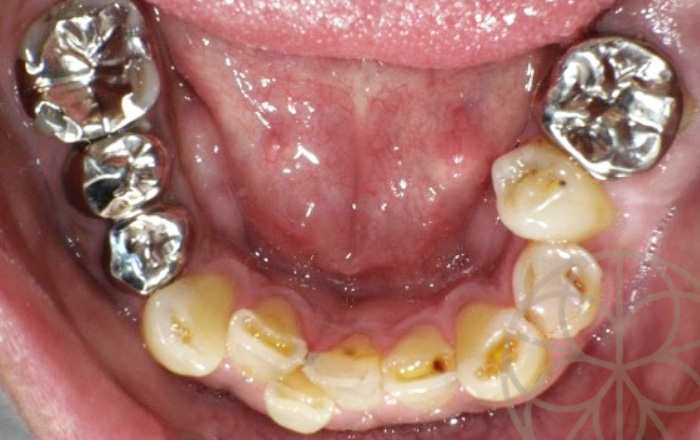

治療前

治療前状況①

30代男性

若い時から歯が悪く、虫歯の再発をくりかえしていたとのことでした。

根尖病巣(根の感染状態)が昔から、よくできいて、歯根端切除(外科的歯内療法)も行っており、その歯もまた再発しており、問題が起こっています。

患者様の要望としては、奥歯も歯がなくて咬めない。前歯にも負担がかかっており、将来的に心配である。

きちんと治療していきたいとのことでした。